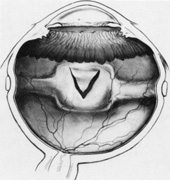

Tenon's capsule is a fascial tissue that invests both the globe and extraocular muscles. Anteriorly it fuses with conjunctiva at the limbus, and posteriorly it ends at the optic nerve sheath. Between Tenon's capsule and the sclera is the interfascial space of Tenon, or simply Tenon's space. Entering this space allows complete exposure of the scleral surface. The extraocular muscles pass through Tenon's capsule, entering Tenon's space to insert on the sclera. At the site of penetration by the individual extraocular muscles, Tenon's capsule reflects posteriorly around the muscles for 10 to 12 mm to form the muscle sheaths. The muscle sheaths are connected by the intermuscular membrane, which, in turn, is connected to the orbital wall by complex fascial arrangements. The retinal surgeon is most concerned with the extraocular muscles after they pass through Tenon's capsule (Fig. 1). At this point they do not possess a muscle sheath but, rather, are invested by episcleral tissue that fuses with the muscle. This tissue forms the falciform folds that fan out from the edges of the muscle to the overlying Tenon's capsule (Fig. 2).

Fig. 2. Relationship of falciform folds to Tenon's capsule and extraocular muscles.